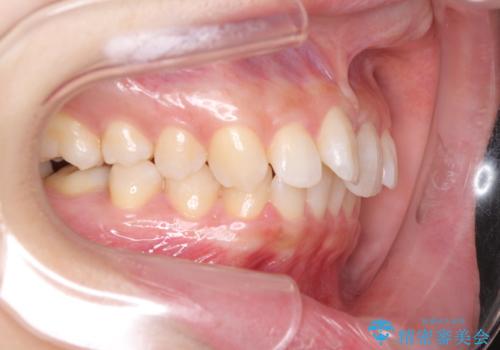

- 前歯のデコボコと奥歯の不正咬合を気にして来院された患者様です。

左右の大臼歯が全て鋏状咬合(シザーズバイト)になっており、治療が難航することが予想されましたが、インビザラインにより治療を行うこととしました。